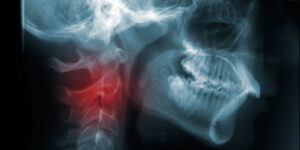

Рак головы и шеи

Виды рака головы и шеи

Существует 5 основных видов рака головы и шеи, каждый из которых назван в соответствии с той частью тела, где он обнаружен.

- Рак гортани и гипофарингеальный рак. Гортань – составная часть голосового аппарата. Этот трубчатый орган на шее предназначен для дыхания, разговора и глотания. Он расположен в верхней части дыхательного горла, или трахеи. Гипофаринкс (пищевод) – нижний отдел горла, окруженный гортанью.

- Рак полости носа и околоносовых пазух. Носовая полость — это пространство позади носа, откуда воздух попадает в горло. Околоносовые пазухи — это заполненные воздухом области, окружающие носовую полость.

- Рак носоглотки. Носоглотка — это воздушная полость в верхней части глотки за носом.

- Рак ротовой полости и ротоглотки. Полость рта включает в себя рот и язык. Ротоглотка включает в себя середину горла, от миндалин до кончика голосового аппарата.

- Рак слюнных желез. Слюнная железа вырабатывает слюну. Слюна — жидкость, которая выделяется во рту для поддержания его влажности и содержит ферменты, расщепляющие пищу.